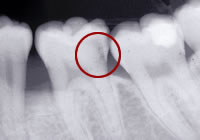

虫歯、歯周病の問題を解決した上で矯正治療を行い、

矯正治療終了後、矯正治療では不可能な微妙なかみ合わせの調整をして、

全身とかみ合わせのバランスを整えます。(→かみ合わせ治療) |

| 私が最も心を痛めているのは他院での矯正治療の結果、 |

| …このような患者さんが時々来院されることです。 |

・健康な歯

・健康な歯肉(歯周組織)

・全身とのバランスがとれたかみ合わせ(→かみ合わせ治療) |

| この3つがすべてそろうことで矯正治療は成立します。 |